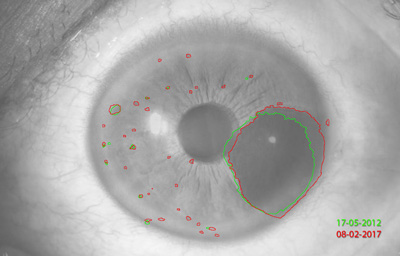

Melanocitomas

Melanocitoma es una lesión benigna, profundamente pigmentada, variante del, nevus uveal que fue originalmente descrito por Zimmerman y Garron en 1962 en el nervio óptico; ahora se sabe que puede aparecer en cualquier lugar del tracto uveal.

Son masas con algo de elevación, con pigmento marrón oscuro casi negro, frecuentemente con apariencia de “ montículo de arena negra”. Sus células son ovoides con núcleos uniformes, pequeños y muy pigmentados. pueden generar satélites en el estroma o en el ángulo de la cámara anterior. Pueden evolucionar a Melanoma (30)

Archivo Fotográfico Dr. Francisco Barraquer. 2012

Archivo Fotográfico Dr. Francisco Barraquer. 2017

Estudio comparativo